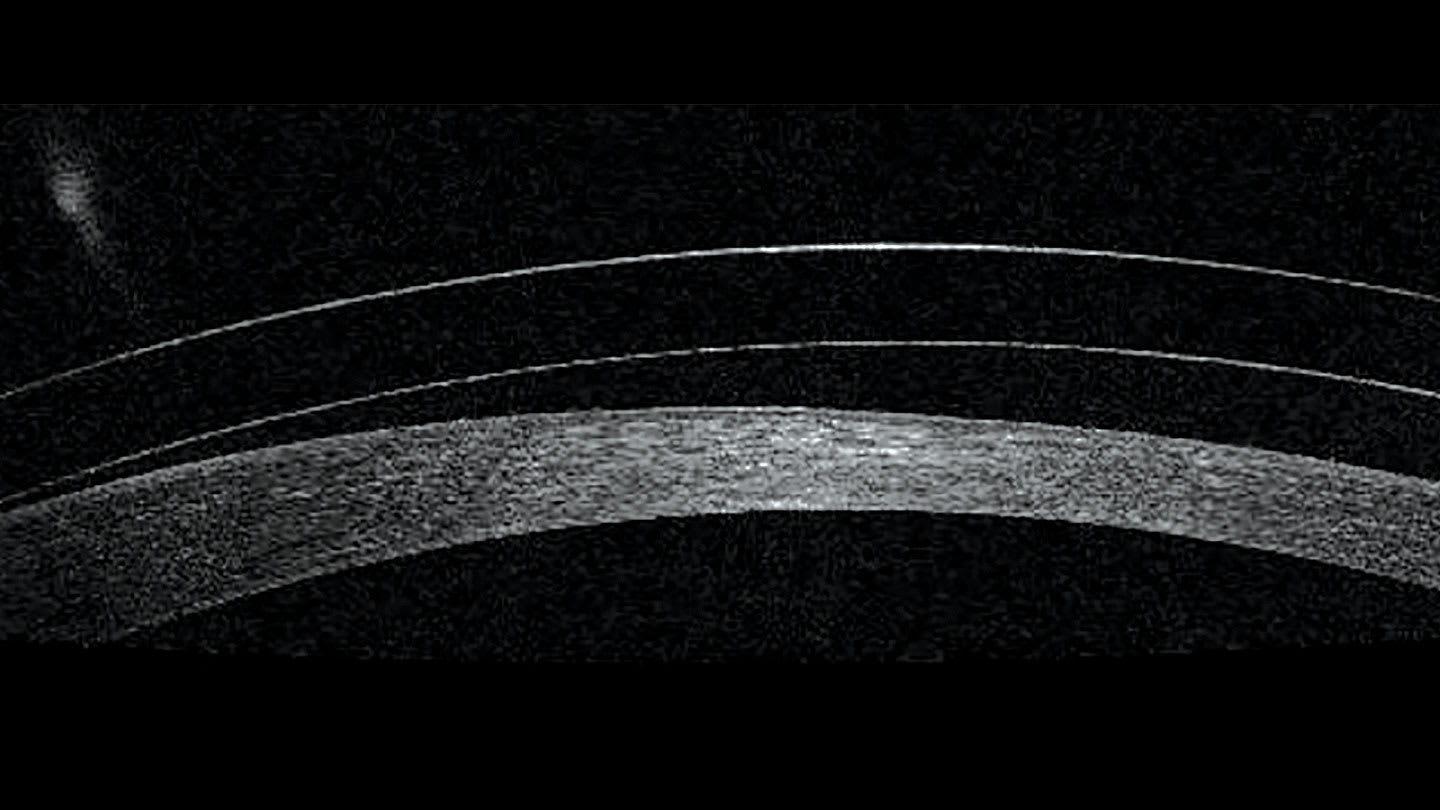

Selecting a base curve that is much steeper than the patient’s cornea will end up with an excessively plus tear reservoir between the lens and the cornea (Figure 1 vs Figure 2). A high minus over-refraction will result, and the resulting lens power will have to be ordered to allow the patient to see clearly. Conversely, if a base curve is flatter compared to the corneal curvature, a minus tear reservoir will be created, creating a need for a plus power to achieve clarity with the lens.